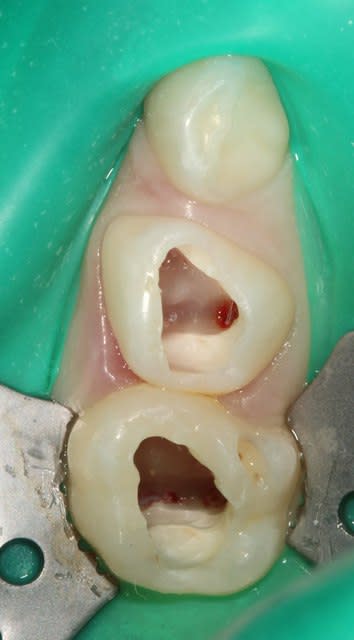

Voilà, premier cas (il y a un début à tout) où j'ai posé la digue pour un soin de A à Z sur un môme de 8ans pour soigner sa 55.

Pour le choix de l'amalgame, j'avoue mon incapacité totale à recréer un vrai point de contact sur les dents de lait avec un délabrement aussi important.